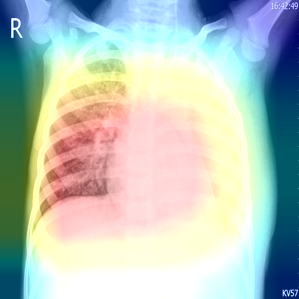

In order to compare the interpretability capacity of our model and the state-of-the-art models, we employ Grad-Cam [18] for heatmap visualizations on selected X-ray images. We show on a side-by-side basis how our model performs with superiority in Figures 4-7. We also observe that the addition of the attention block has a crucial role in focusing on the most relevant features in the images, which significantly assists the model during classification.